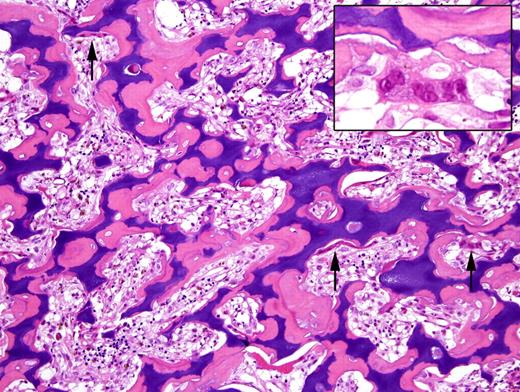

Photomicrograph of a bone biopsy from a patient with osteopetrosis, stained with haematoxylin-eosin. The amount of bone is markedly increased and represented by primary spongiosa (calcified cartilage rimmed by osteoid tissue). Note the numerous osteoclasts (arrows), laying along the trabeculae surface, without evidence of bone resorption (inset). Lacunae are obviously narrowed and the hematopoetic tissue reduced (courtesy of Professor F. Facchetti, Department of Pathology, University of Brescia, Italy).

Genetic defects of the TCIRG1 gene, encoding for a subunit of the osteoclast proton pump essential for bone resorption, account for osteopetrosis in oc/oc mice and for 50% to 60% of all cases of AR osteopetrosis in humans. In this form, osteoclasts are present, but they are unable to mediate bone remodeling (see figure). HSCT represents the only available cure for severe AR osteopetrosis in humans, with over 70% disease-free survival when a human leukocyte antigen (HLA)–identical donor is available, but with far less satisfactory results when HSCT is performed from HLA-mismatched related donors. Furthermore, conservation of vision and growth is better if the transplantation is performed early in life.4 In this regard, demonstration that neonatal gene therapy can correct osteopetrosis in oc/oc mice is of the utmost importance. Johansson and colleagues have shown that fetal liver cells, transduced with a tcirg1-containing retroviral vector, can be induced to differentiate in vitro into bone-reabsorbing osteoclasts upon culture with macrophage colony-stimulating factor (M-CSF) and receptor activator of NF-kappaB ligand (RANKL). In vivo injection of gene-corrected cells into sublethally irradiated oc/oc mice at day +1 of life resulted in prolonged survival and significant correction of the skeletal phenotype in a significant proportion of cases. However, a number of problems remain to be solved before a similar approach is proposed in humans.